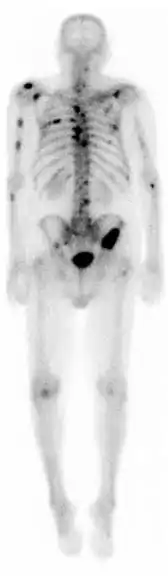

![]() مسح عظام طبي نووي لعظام كامل الجسم (تفريسة ومضانية للعظام).

إن مسح العظام الطبي النووي لعظام كامل الجسم يستخدم بشكل عام في تقييمات مختلف الأمراض المتعلقة بالعظام ، مثل آلام العظام ، أو كسور الإجهاد ، أو آفات العظام غير الخبيثة ، أو التهابات العظام ، أو انتشار السرطان في العظام. | |